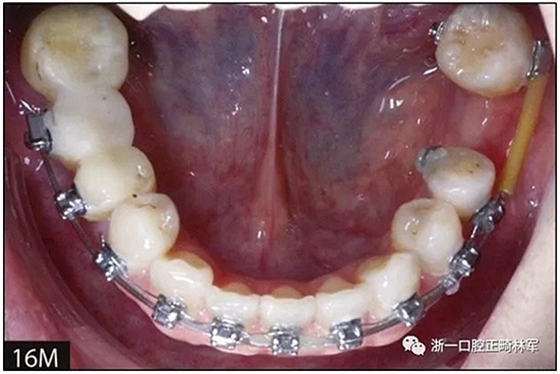

完全固定的Damon Q設備(加利福尼亞州Glendora的Ormco)與制造商指定的弓絲和附件一起使用。下頜弓,一開始放入0.014英寸的鎳鈦弓絲,5個月后放入0.014×0.025英寸的鎳鈦弓絲。舌側扣和鏈圈放置在下頜尖牙和第二前磨牙上以控制扭轉。在治療的第7個月,將下頜弓絲換成0.017× 0.025英寸的β鈦絲。另一個舌側扣和鏈圈放置在下頜左側第三磨牙上以提供近中牽引力(圖9)。在16個月的治療結束時,所有的扭轉都得到了矯正,缺牙間隙縮小到8 mm(圖8),但由于頰側骨板的嚴重吸收,牙槽嵴的寬度仍然很窄(約3 mm)(圖9)。通過正畸移動下頜左側第二前磨牙,在前磨牙之間產(chǎn)生一個種植部位。在第一和第二前磨牙之間的弓絲上放置一個推簧,并將舌側扣和鏈圈放置在第一前磨牙和第三磨牙之間(圖9),在頰側和舌側施加力。施力均為輕力,每個表面上約2盎司(28.3 cN)以控制牙根側面的吸收。

圖10.經(jīng)過7個月后,以每月1毫米的速度牽引下頜左側第二前磨牙,正畸產(chǎn)生的種植部位長約7毫米。通過使用固定矯治器保持間隙6個月。根尖X線片顯示第二前磨僅有少量牙根遠中面吸收。